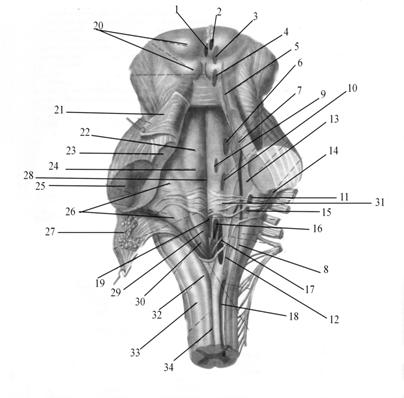

Необычные объекты: Переднее продырявленное вещество

Раздел: Альбом открытий